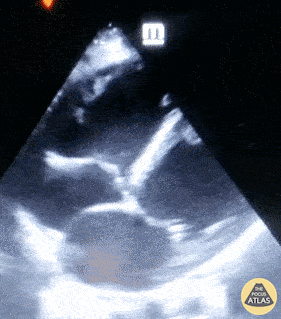

A 30-year-old male with history of idiopathic heart failure was hospitalized and on mechanical ventilation for COVID-19. POCUS included this subcostal image notable for severe bi-ventricular dysfunction complicated by thrombus formation in the left and right ventricles. Patricia Lopes, Resident of Emergency Medicine at Fortaleza-CE, Brazil @patylopes90